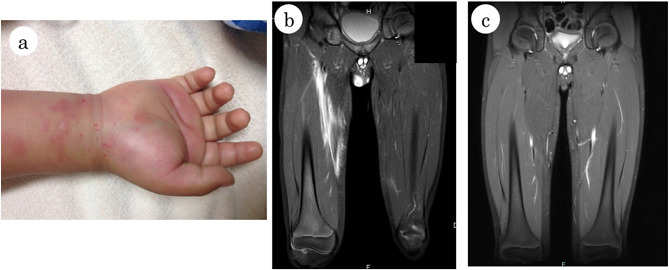

Case presentation: The patient developed a high fever and skin swelling with pain and erythema on the right side of his body following an abrasion injury on his right wrist at the age of 5 years, and was suspected of having streptococcal toxic shock-like syndrome, for which he received antimicrobials, immunoglobulin therapy, debridement, and plasma exchange. The same manifestations with similar magnetic resonance imaging (MRI) findings of high signal on short tau inversion recovery showing the spread of inflammation in the fat tissue and fascia was observed twice at the age of 6 years. Serological analyses for conventional autoantibodies, bone marrow aspiration, and whole-exome sequencing examination were non-remarkable. Prednisolone was effective in ameliorating the above putative autoinflammatory syndrome. The patient was admitted at the age of 10 years with similar clinical and MRI findings indicative of recurrence of the same disease. En bloc biopsy from the skin to the fascia showed thickening of collagen fibers, infiltration of inflammatory cells composed mainly of neutrophils and lymphocytes, and necrotizing vasculitis in the fat tissue and fascia. Immunohistochemical staining of the en bloc biopsy sections indicated infiltration of T lymphocytes and macrophages in the perivascular connective tissue and fibrinoid necrosis, supporting the diagnosis of FPS. Induction therapy with prednisolone resulted in a remission. IgG purified from the patient's serum reacted with pericellular basement membranes in the subcutaneous fat tissue by immunohistochemistry. The patient is currently taking famotidine to prevent relapses and is making good progress in his recovery.